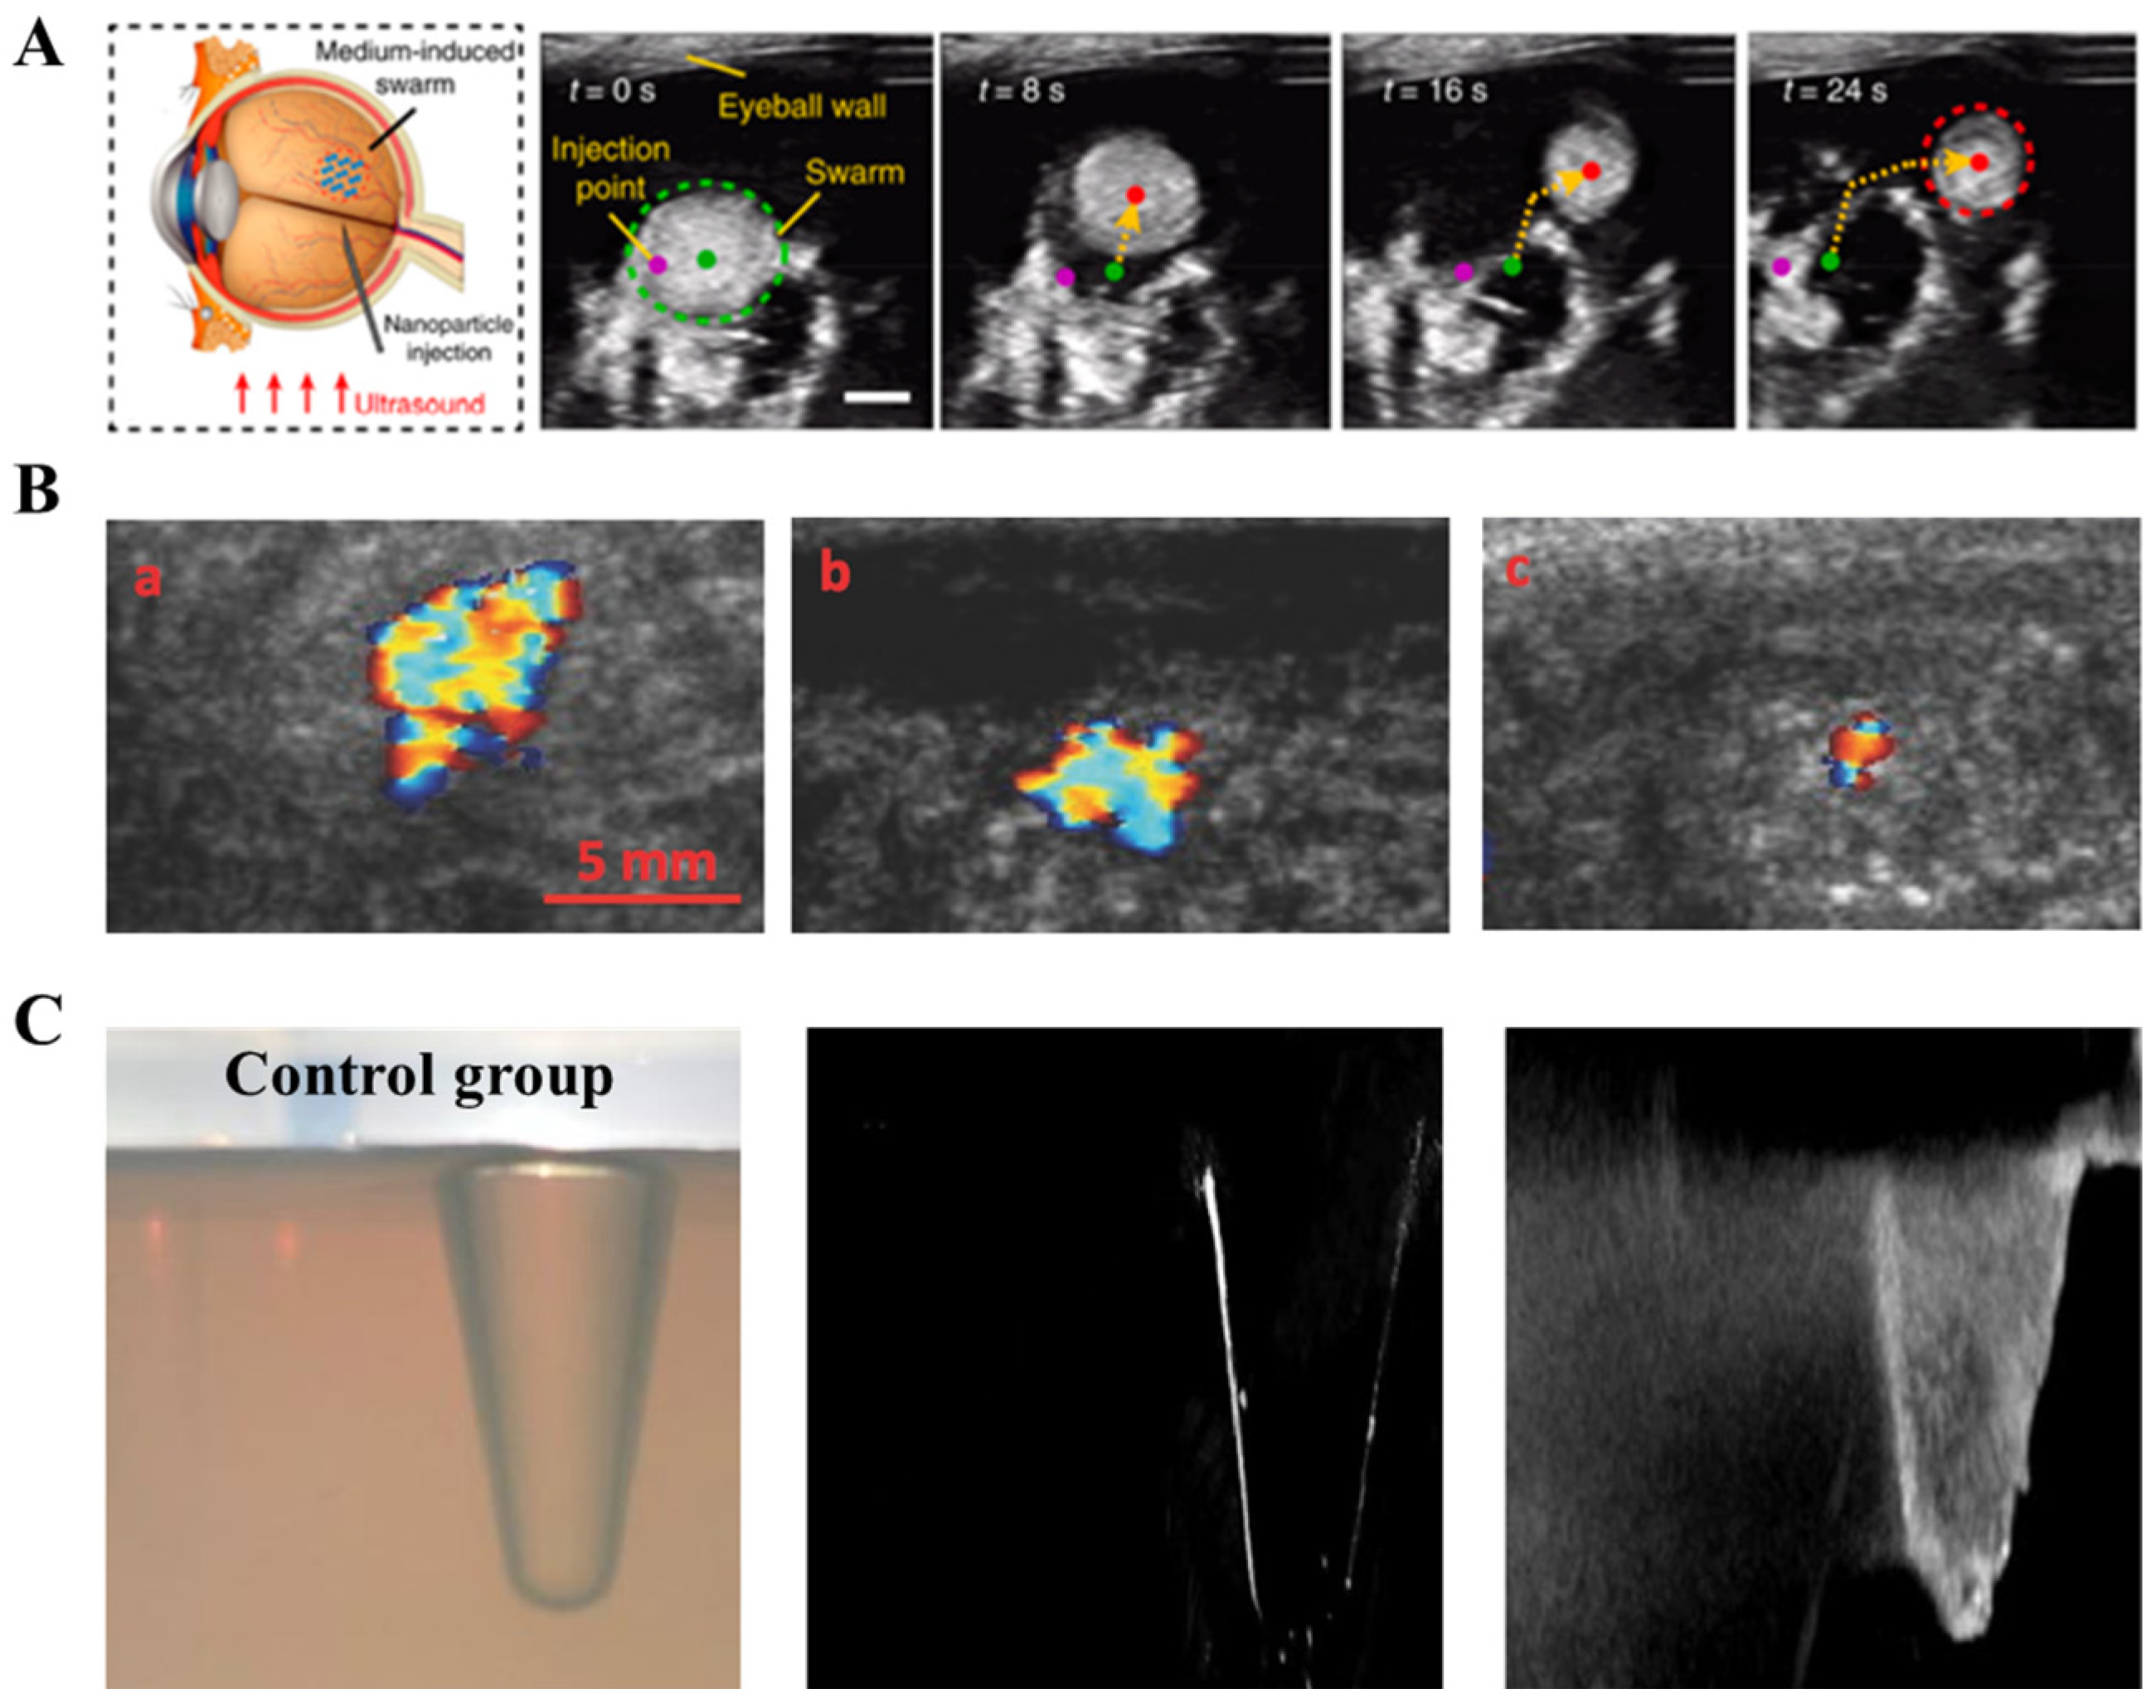

2.3. Ultrasound Imaging (Ultrasound)

- Wang, Q.Q.; Zhang, L. Ultrasound imaging and tracking of micro/nanorobots: From individual to collectives. IEEE Open J. Nanotechnol. 2020, 1, 6–17. [Google Scholar] [CrossRef]

- Yu, J.; Jin, D.; Chan, K.F.; Wang, Q.; Yuan, K.; Zhang, L. Active generation and magnetic actuation of microrobotic swarms in bio-fluids. Nat. Commun. 2019, 10, 5631. [Google Scholar] [CrossRef] [PubMed]

- Yu, J.; Wang, Q.; Li, M.; Liu, C.; Wang, L.; Xu, T.; Zhang, L. Characterizing nanoparticle swarms with tuneable concentrations for enhanced imaging contrast. IEEE Robot. Autom. Lett. 2019, 4, 2942–2949. [Google Scholar] [CrossRef]